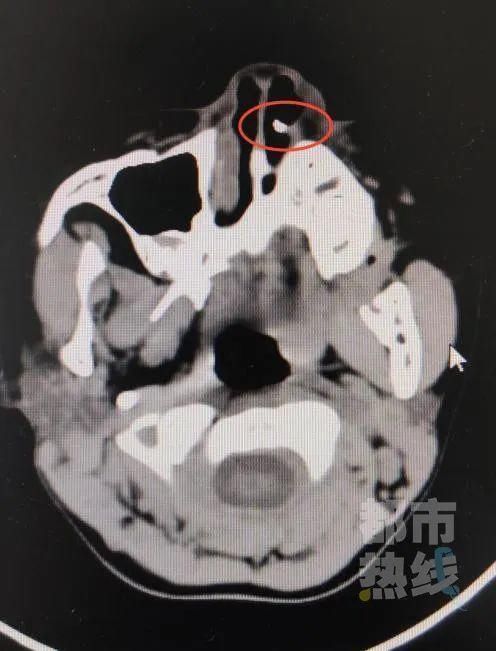

近日,西安市第三医院接诊了一位6岁女童患者。孩子的鼻腔不适,通气不好。为孩子进行仔细查体后,医生发现在她的左侧鼻腔底部有一白色凸起,触之质硬。

CT片子上显示在孩子的

左侧鼻腔里竟然有一个

白色高密度异物影

一颗牙